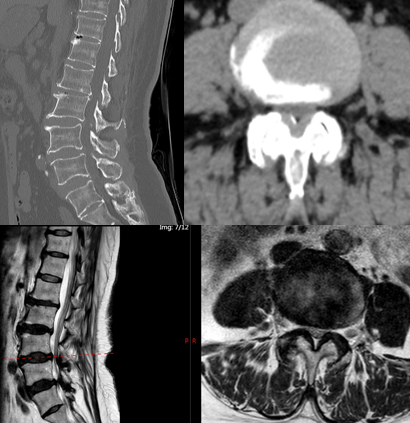

病例

男,64岁。

主诉:腰痛2年、加重伴左下肢疼痛麻木4个月,左小腿后外侧为著。

术后复查

思考和建议:

术前停用抗凝药

术中彻底止血(特别是骨面的出血)

尽量减少骨性结构破坏

放置引流管

避免水压过大(<30mmHg)

一旦出现神经症状,尽早手术(12小时内)